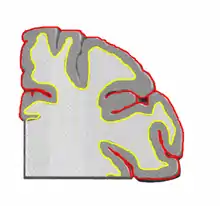

قشر مخ لایه نازکی از جنس ماده خاکستری است سطح مغز را می پوشاند.قشر مخ مرکز بسیاری از اعمالات ارادی بدن و مرکز پردازش اطلاعات حسی در مغز می باشد که چین خوردگی های این لایه به پردازش بهتر اطلاعات حسی کمک می نماید.این لایه از سلولهای عصبی مغز تشکیل شده است.علت خاکستری رنگ بودن این لایه بیرونی مخ، تجمع جسم سلولی ( پریکاریون) یاخته های عصبی تشکیل دهنده آن می باشد.ضخامت آن در نواحی مختلف مغز متفاوت است اما تقریباً در همه جا ضخامتی بین ۲ تا ۴ میلیمتر دارد.

| FMA | 61830 |